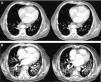

The computed tomography results are shown in Fig. 1, while the bronchoscopy study only showed supraglottal polypoidal lesions. Bronchial aspiration cytology was negative for neoplastic cells.

Evolution of the pulmonary involvement shown by axial computed tomography (ACT). (A) ACT of the thorax at diagnosis revealed the presence of discrete interstitial infiltrates in ground glass opacity in the bases and periphery of the lungs, and to a lesser degree, in the mid-fields, with multiple mediastinal lymphatic ganglia of less than 17mm and segmental atelectasis of the lower right lobe. (B) At 3 months the angio ACT showed no images of pulmonary thromboembolism, although extensive bilateral involvement of the lungs was observed, with interstitial infiltrates with ground glass opacity and interlobular septal thickening, as well as areas of fibrosis, while the anterior pulmonary fields were less involved.